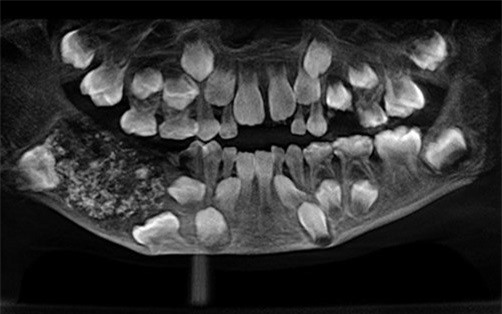

Cậu bé 7 tuổi có đến 526 cấu trúc giống răng trong miệng

Cấu trúc giống răng của cậu bé. (Ảnh:Saveetha Dental College and Hospital). |

Theo nguồn tin từ bệnh viện, các bác sĩ đã mất đến 5 tiếng để loại bỏ toàn bộ các cấu trúc răng trong hàm cậu bé. Những cấu trúc răng có kích thước từ 1mm đến 15mm, mỗi mẩu răng đều được bao phủ bởi lớp men khá hoàn chỉnh.

Bệnh viện chữa trị cho biết: “Đây là trường hợp đầu tiên được ghi nhận trên toàn thế giới về hiện tượng kỳ lạ này, một người có từng ấy nang răng trong miệng. Bệnh lý hiếm gặp này có tên là “u răng đa hợp” (compound odontome).

Theo nghiên cứu của Học viện Nhi Nha khoa Mỹ, u răng đa hợp là sự phát triển bất thường khiến các khối u hình thành từ men răng được một lớp ngà răng bao phủ. Bệnh lý này thường được phát hiện ở những người trong độ tuổi 20 nhưng cũng có thể được chẩn đoán ở mọi lứa tuổi.

Năm 3 tuổi, cậu bé đã được bố mẹ đưa đi khám vì bị sưng hàm nhưng do cậu còn quá bé nên không chịu hợp tác với bác sĩ. Các vết sưng vẫn tiếp tục gia tăng khi cậu lớn lên. Bệnh viện vẫn chưa xác định chính xác thời điểm phẫu thuật cắt bỏ các nang răng để ngăn các u răng phát triển trở lại.